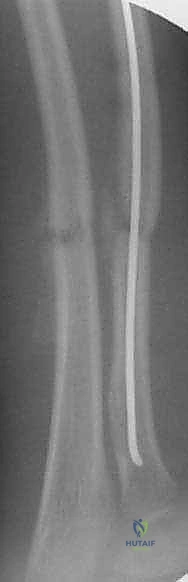

تُعد تقنية التثبيت بالمسامير المرنة داخل النخاع (Flexible Intramedullary Nailing - FIN) أو مسامير التيتانيوم المرنة (Titanium Elastic Nails - TENs) المعيار الذهبي (Gold Standard) لعلاج كسور الساعد غير المستقرة لدى الأطفال. والأستاذ الدكتور محمد هطيف هو رائد هذه التقنية في اليمن.

مبدأ عمل المسامير المرنة

على عكس الشرائح والمسامير التقليدية (Plates and Screws) التي تتطلب شقوقاً جراحية كبيرة وتؤدي إلى تقشير السمحاق (مما يضعف التروية الدموية للعظم)، تعمل المسامير المرنة بمبدأ مختلف تماماً.

يتم إدخال مسمارين مرنين (عادة من التيتانيوم أو الصلب الطبي المقاوم للصدأ) داخل التجويف النخاعي (Marrow Canal) للعظم. يتم ثني هذه المسامير مسبقاً بواسطة الجراح لتشكيل قوس. عندما يتم إدخالها في العظم، فإنها تعمل بمبدأ "التثبيت ثلاثي النقاط" (Three-Point Fixation). تولد المسامير المرنة قوة شد داخلية تدفع أجزاء العظم المكسور نحو بعضها البعض، مما يوفر استقراراً حيوياً ميكانيكياً (Biomechanically Stable) يسمح بتكوين الكالس (Callus) وشفاء العظم بسرعة فائقة.

مميزات تقنية المسامير المرنة مع أ.د. محمد هطيف:

- تدخل جراحي طفيف (Minimally Invasive): شقوق جراحية صغيرة جداً (1-2 سم) لإدخال المسامير، مما يعني ندبات شبه معدومة وألماً أقل بكثير بعد الجراحة.

- الحفاظ على التروية الدموية: عدم فتح موقع الكسر (في معظم الحالات) يحافظ على الورم الدموي الخاص بالكسر (Fracture Hematoma) والسمحاق، مما يسرع من التئام العظم بشكل طبيعي.

- الحفاظ على صفائح النمو: يتم إدخال المسامير بحذر شديد لتجنب إصابة صفائح النمو المسؤولة عن طول العظم مستقبلاً.

- نتائج تجميلية ووظيفية ممتازة: استعادة كاملة للانحناء الطبيعي للكعبرة وحركة الساعد.